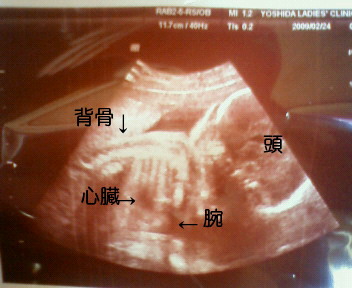

妊婦健診 妊娠24週 妊娠7ヶ月 エコー写真 逆子 赤ちゃんの体重 お腹の大きさ Natsumin Blog 中村夏海のブログ

妊娠24週目 24w0d 6d のエコー写真とエピソード 妊娠7ヶ月 Cozre コズレ 子育てマガジン

妊娠24週 赤ちゃんのエコー写真 超音波写真まとめ たまひよ